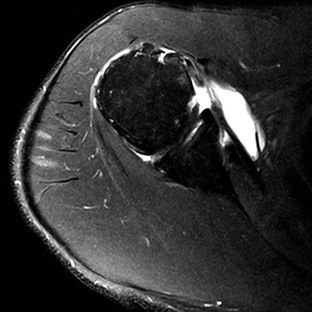

Although conventional MRI is established as the imaging modality of choice in the evaluation of shoulder impingement syndrome, MRA is accepted as the method of choice for the evaluation of glenohumeral instability.22,23 Many of the lesions associated with instability are subtle and may undergo partial healing. This situation, coupled with the fact that the normal anatomic structures of the shoulder lie in close proximity, can make the diagnosis of these lesions difficult even with high-quality conventional MRI.58-62 MRA, on the other hand, is performed by distending the joint with fluid (saline solution or dilute gadolinium), which more accurately depicts subtle labral tears, cartilage and ligamentous abnormalities, and partial-thickness tears of the undersurface of the rotator cuff. The standard injection technique for MRA of the shoulder is described in previous sections. About 12 to 14 mL of gadolinium diluted 1 : 200 with normal saline solution or 1% lidocaine is injected. Imaging protocols vary, but a standard set of imaging sequences typically includes T1-weighted images with frequency-selective fat saturation in the axial, oblique sagittal, and oblique coronal planes. The T1-weighted images have a high signal/noise ratio, resulting in the anatomic detail that is critical in detecting the subtle lesions associated with glenohumeral instability. A T2-weighted sequence performed in the oblique coronal plane is the most important sequence for depicting rotator cuff abnormalities. A T2-weighted sequence may also be helpful in detecting other pathologic processes, such as a paralabral cyst or bone marrow edema (Fig. 44-7, A and B). The ABER view may be added to the standard imaging protocol for any patient thought to have an anterior labral pathologic process.54

Anterior and lateral downward sloping of the anterior acromion can also narrow the supraspinatus outlet and potentially result in impingement.80,81 Anterior downward sloping (see Fig. 44-11, B) is demonstrated on oblique sagittal MRI; lateral downward sloping (see Fig. 44-11, C) is best seen on the oblique coronal images. An enthesophyte (Fig. 44-12) extending off the anteroinferior aspect of the acromion can also be clearly demonstrated on MRI. It typically appears as a marrow-containing osseous excrescence, which should have MRI signal characteristics similar to those of the adjacent acromion marrow (bright on T1-weighted images). Potential pitfalls include the attachment of the coracoacromial ligament and the deltoid tendon insertion (see Fig. 44-11, A and C) on the anterior acromion. These structures may mimic an osseous excrescence, but they can be differentiated from enthesophytes because they lack marrow signal and appear dark on all pulse sequences. The acromion should also be evaluated for os acromiale (Fig. 44-13), which is an accessory ossification center along the outer edge of the anterior acromion. It is normally fused by 25 years of age. An association exists between persistent os acromiale and impingement of the rotator cuff.82-86 The deltoid muscle attaches to the inferior aspect of the accessory ossicle, and contraction of the deltoid results in a downward motion of the unstable segment, potentially leading to impingement of the underlying rotator cuff. Os acromiale is demonstrated best on axial images (see Fig. 44-7, A), but it can also be seen on oblique sagittal or oblique coronal images (see Fig. 44-7, B),85 on which it should not be confused with the adjacent AC joint. MRI signs of instability of the os acromiale include fluid signal within the synchondrosis or sclerosis, cystic change, or marrow edema on either side of the synchondrosis (Box 44-2).